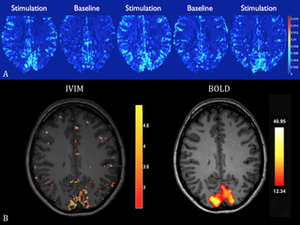

- 3.43 Functional Mapping of the Human Visual Cortex with Intravoxel Incoherent Motion MRI